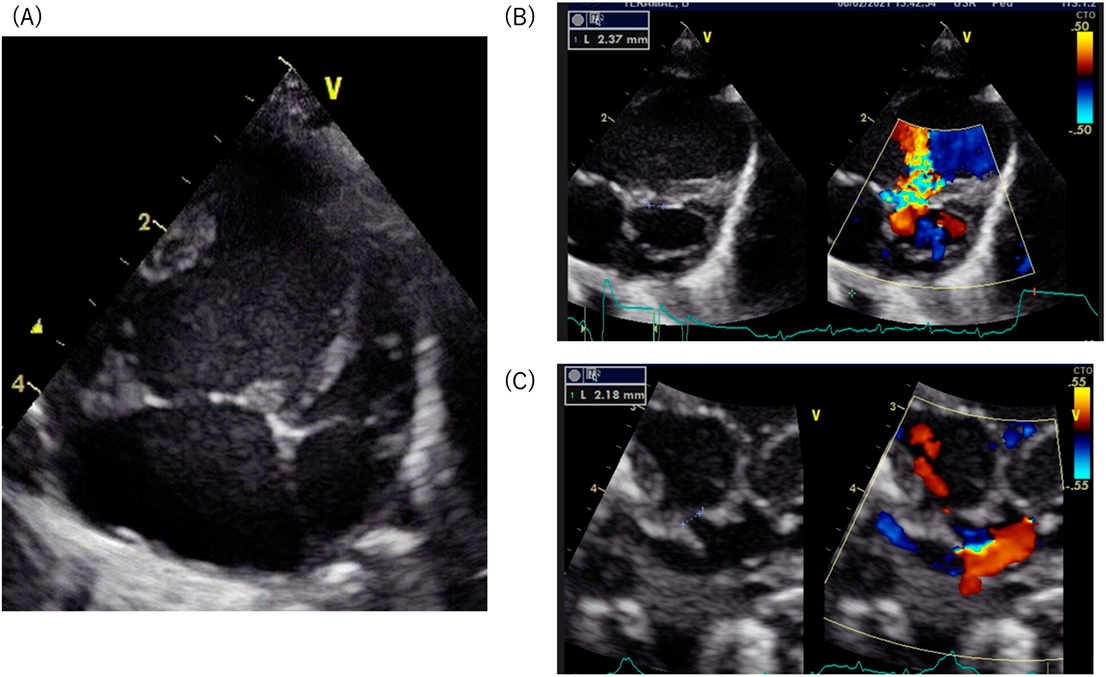

Fig. 1 (A) Four-chamber view of the heart showing hypoplasia of the left atrium and the left ventricle. (B) Color-doppler imaging showing a small ventricular septal defect. The diameter of the defect is 2.37 mm. (C) Color-doppler imaging showing a small foramen ovale.

The diameter of the communication is 2.18 mm.